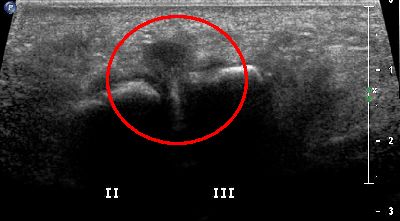

Neuroma di Hauser

Neuroma di Hauser del secondo spazio intermetatarsale (img. 01) Neuroma Hauser 01